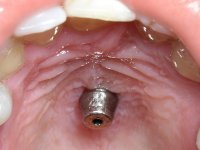

Os cotos de óxido de zircónio são dos assuntos mais debatidos em implantologia. A sua resistência à fractura, as conexões externas e internas, a interacção entre o parafuso de retenção e o coto – todos estes assuntos são abordados repetidamente. No entanto, todos parecem concordar que os cotos de óxido de zircónio apresentam resultados altamente previsíveis, especialmente na restauração de dentes anteriores. Outro argumento em favor dos cotos de óxido de zircónio é a alta biocompatibilidade do material.

A comparação entre o óxido de zircónio e o dissilicato de lítio mostra que o último pode sofrer ataque ácido e ser silanizado e assim ser preparado para uma cimentação adesiva. Uma dica: no sentido de criar no coto de óxido de zircónio uma superfície susceptível de ser gravada pelo ácido, a superfície a ser colada pode ser recoberta com uma fina camada de cerâmica de adesão antes de modelar a coroa. Para este propósito, a ceram Zirliner é aplicada primeiro, depois aplica-se uma camada de ceram de dentina profunda na tonalidade desejada. Como resultado, a cor da dentina ilumina a restauração a partir do seu interior e cria a possibilidade de ser aplicado um protocolo de cimentação adesiva.